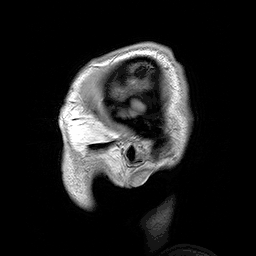

Many people with abnormally large heads or large skulls are healthy, but macrocephaly may be pathological. Pathologic macrocephaly may be due to megalencephaly (enlarged brain), hydrocephalus (abnormally increased cerebrospinal fluid), cranial hyperostosis (bone overgrowth), and other conditions. Pathologic macrocephaly is called "syndromic", when it is associated with any other noteworthy condition, and "nonsyndromic" otherwise. Pathologic macrocephaly may be caused by congenital anatomic abnormalities, genetic conditions, or by environmental events.[2]

In research, cranial height or brain imaging may be used to determine intracranial volume more accurately.[2]